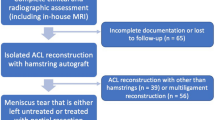

MRI examinations were performed using the department protocol with the patient in the supine position and the knee extended (a maximum of 10° of slight flexion of the knee was allowed in case of marked effusion) on a 3-T whole-body scanner (Skyra, Siemens Healthineers, Er- langen, Germany) using a 6-channel flex coil. MRI was performed within 3 weeks from trauma. Three plane (sagittal, coronal, and axial) sequences using both proton density– and fat-suppressed proton density–weighted images were performed with repetition time (TR) between 3000 and 4000 ms, echo time (TE) between 33 and 35 ms, matrix between 320 × 320 and 384 × 384 (phase x frequency) with 3-mm slice thickness, and a total field of view of 130 mm.

Axial femorotibial alignment

Two sports knee surgery fellows (LF and AM) independently analyzed all MRI images obtained before surgery. To measure the axial alignment of the distal femur and proximal tibia, two sections were identified from each MRI as described by previous studies [11, 12]. The first slice was taken in the midthrochlear region of the femoral condyle, identified by the Roman arch appearance of the intercondylar groove with the apex of the Roman arch corresponding to 1/3 of the height of the condyle. The surgical epicondylar axes (SEA) from the lateral epicondyle and medial sulcus were delineated. The second slice was taken in correspondence with the proximal tibial plateau above the end of the proximal tibiofibular joint where the semimembranosus tendon inserts into the tibial bone. The tangent line of the posterior tibial condyles (PTC) was delineated. The angle between SEA-PTC was measured (Fig. 2). A negative value was defined as internal torsion and a positive value as external torsion of the distal segment.